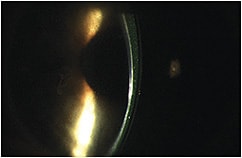

Patients may need to perform additional cleaning of their lenses beyond daily disinfection to remove stubborn deposits, so you may recommend extra strength cleaners or treatments. Do not forget to check application plungers, which can leave residue on the lens surface if not in good condition (Figure 1).